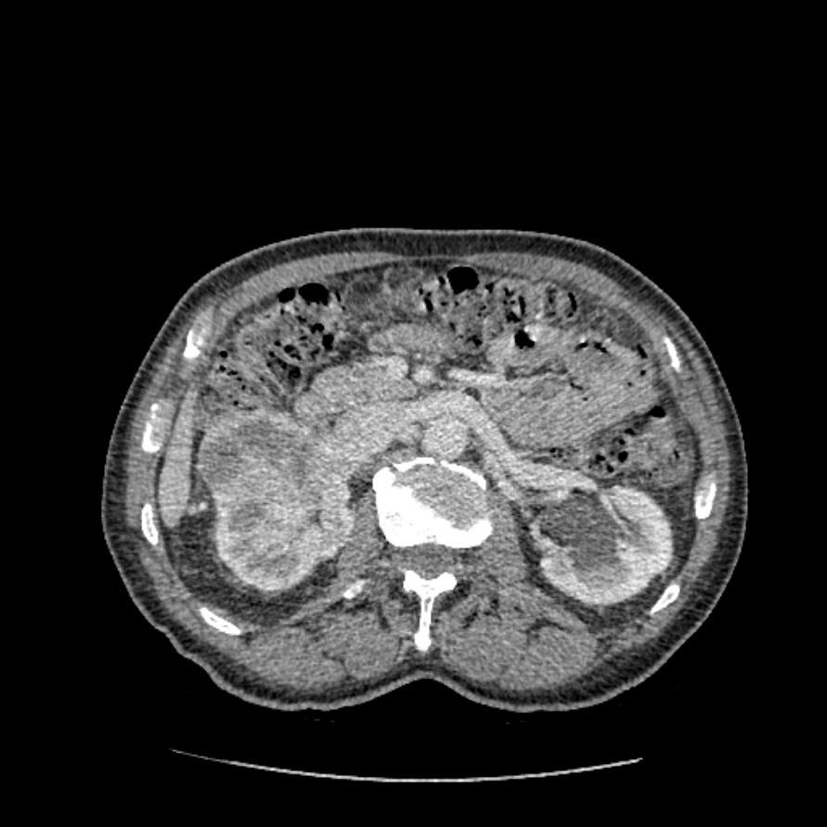

Diagnostic?

Petite tumeur rénale droite trouvée de manière fortuite sur un scanner